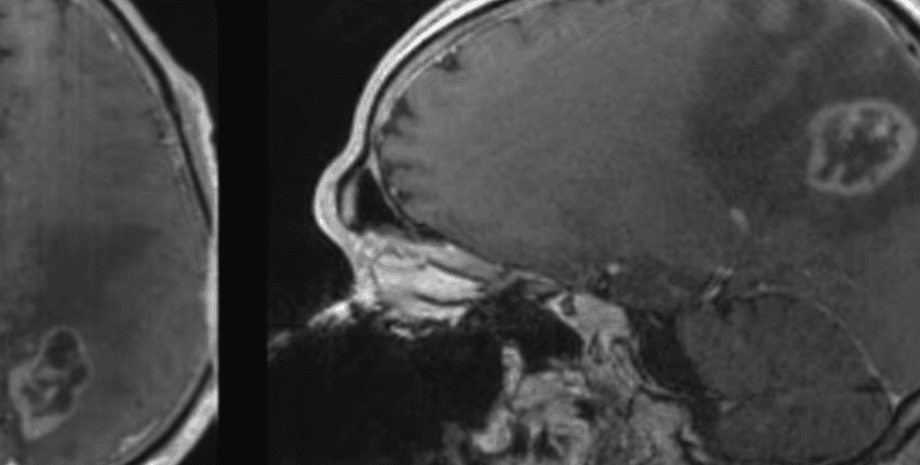

МРТ-изображение глиобластомы | Фото: Dominique Higgins, MD, PhD

В статье, которую опубликовали ученые, говорится о том, что они выяснили, что клетки глиобластомы особенно подвержены гибели именно от ферроптоза. Они заявили, что это открытие невероятно значимо, так как глиобластома 100% фатальна для больного и не имеет способов лечения. Так же, из-за своей невероятно агрессивной натуры, в среднем она не оставляет больным больше 16 месяцев перед тем как забрать их жизнь.